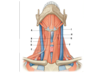

20

Q

What is G?

A

Vertebral artery

21

Q

What is H?

A

Pons

22

Q

What is I?

A

Pituitary gland

23

Q

What is J?

A

Pituitary stalk